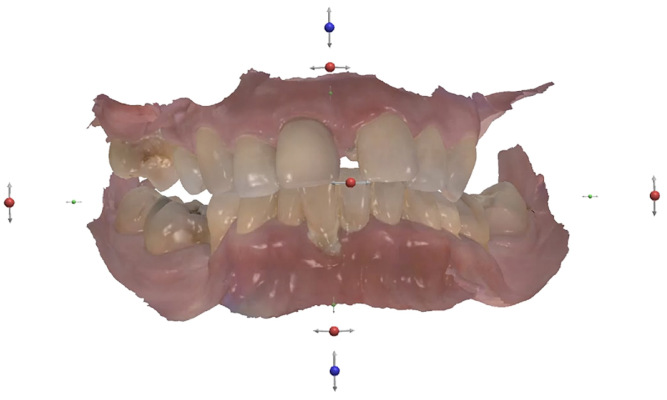

A 57-year-old female patient who was systemically healthy and a non-smoker and had no relevant medical history came to our clinic stating that she was unable to eat without pain and had absolutely no confidence or pride in her smile or overall appearance. She had also noticed flaring and progressive spacing of her anterior teeth and complained of food impaction. She desired a full-mouth fixed rehabilitation and wanted to improve the position of her teeth to regain the confidence to smile.

No abnormalities were found during the extra-oral examination. The patient presented with a low smile line. The intra-oral examination revealed terminal dentition due to generalised periodontal disease. The patient presented with severe resorption of the posterior maxilla bilaterally (Fig. 1). The radiographic examination showed generalised alveolar bone resorption with vertical bone defects (Fig. 2).